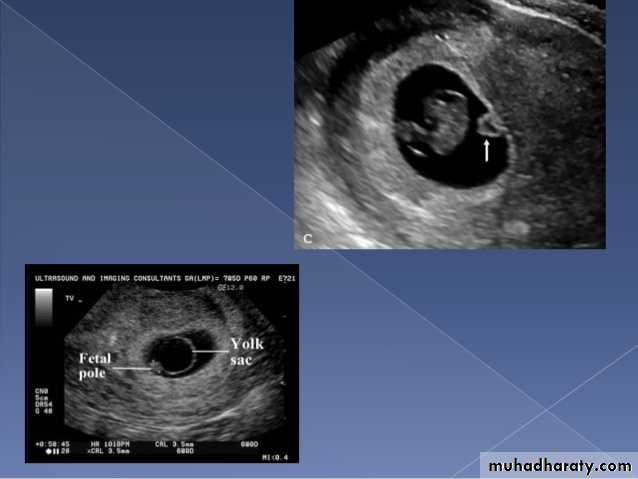

Anembryonic pregnancy is a form of a failed early pregnancy, where a gestational sac develops, but the embryo does not form. The term blighted ovum is synonymous with this, but is falling out of favour and is best avoided.

Radiographic features

Ultrasound

An anembryonic pregnancy may be diagnosed when there is no fetal pole identified on endovaginal scanning , and:

the size of the gestational sac is such that a fetal pole should be seen: MSD ≥25 mm on TVS (by RCOG criteria)